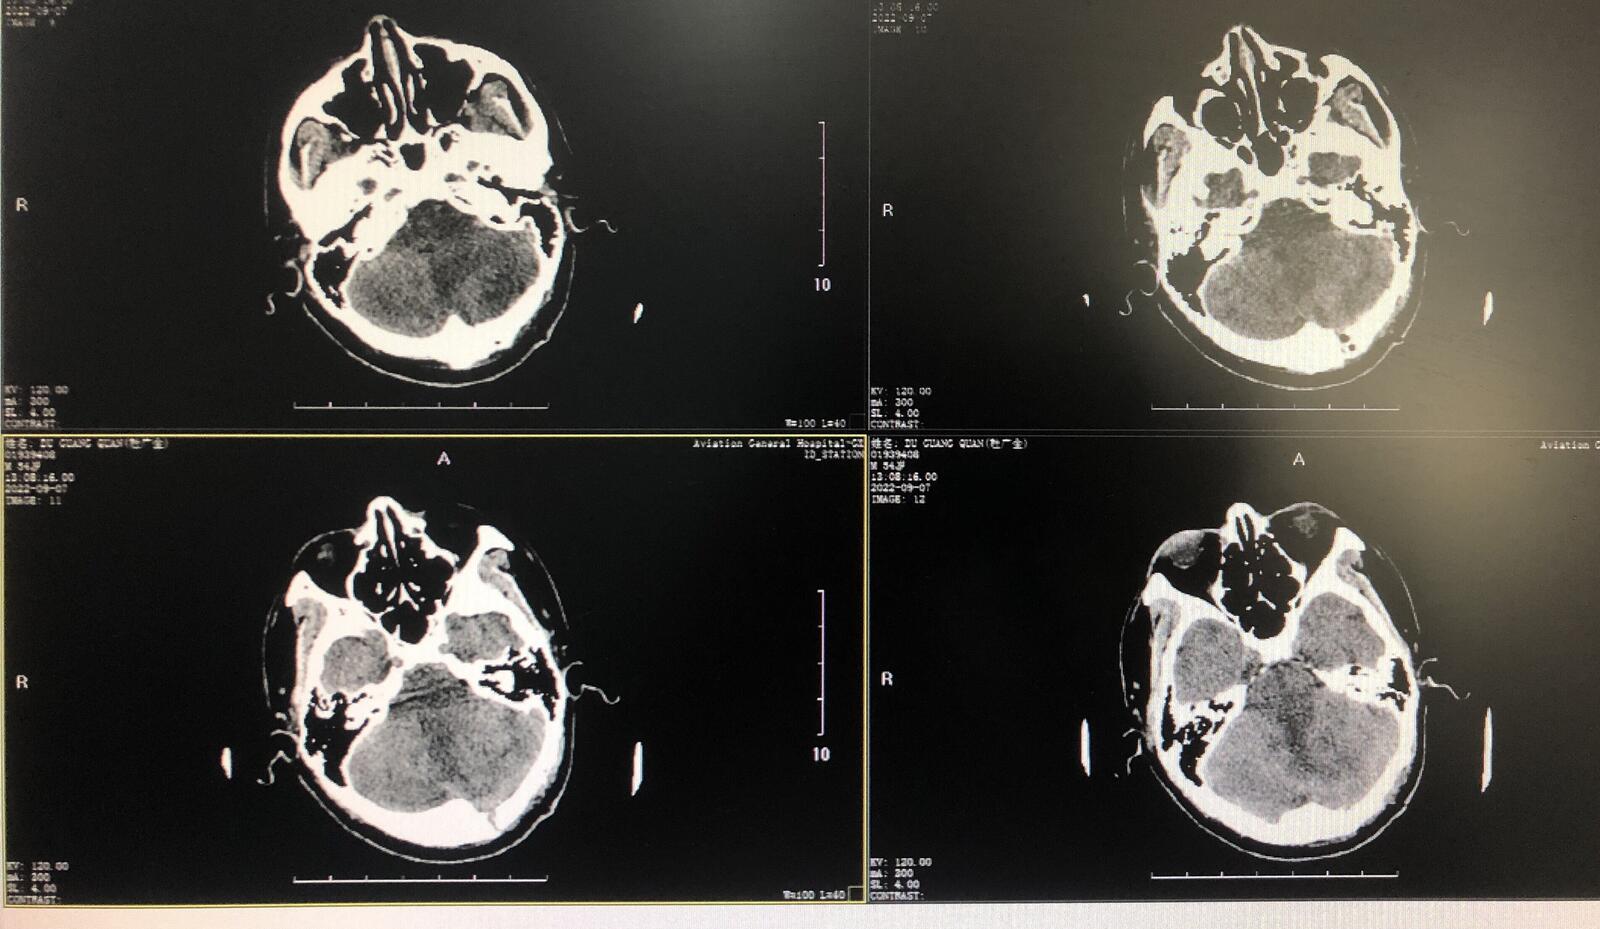

左侧小脑占位:脑膜瘤

患者男性54岁,头晕半年,就诊当地医院查CT提示脑膜瘤?后行头颅核磁提示:左侧小脑半球上方(小脑幕下区域)占位性病变,考虑脑膜瘤。为进一步治疗来我科住院。入院后行左侧旁正中脑膜瘤小脑切除术。术中显微镜下切开小脑幕分离切除肿瘤。术后症状好转,伤口愈合好,恢复好。

术后